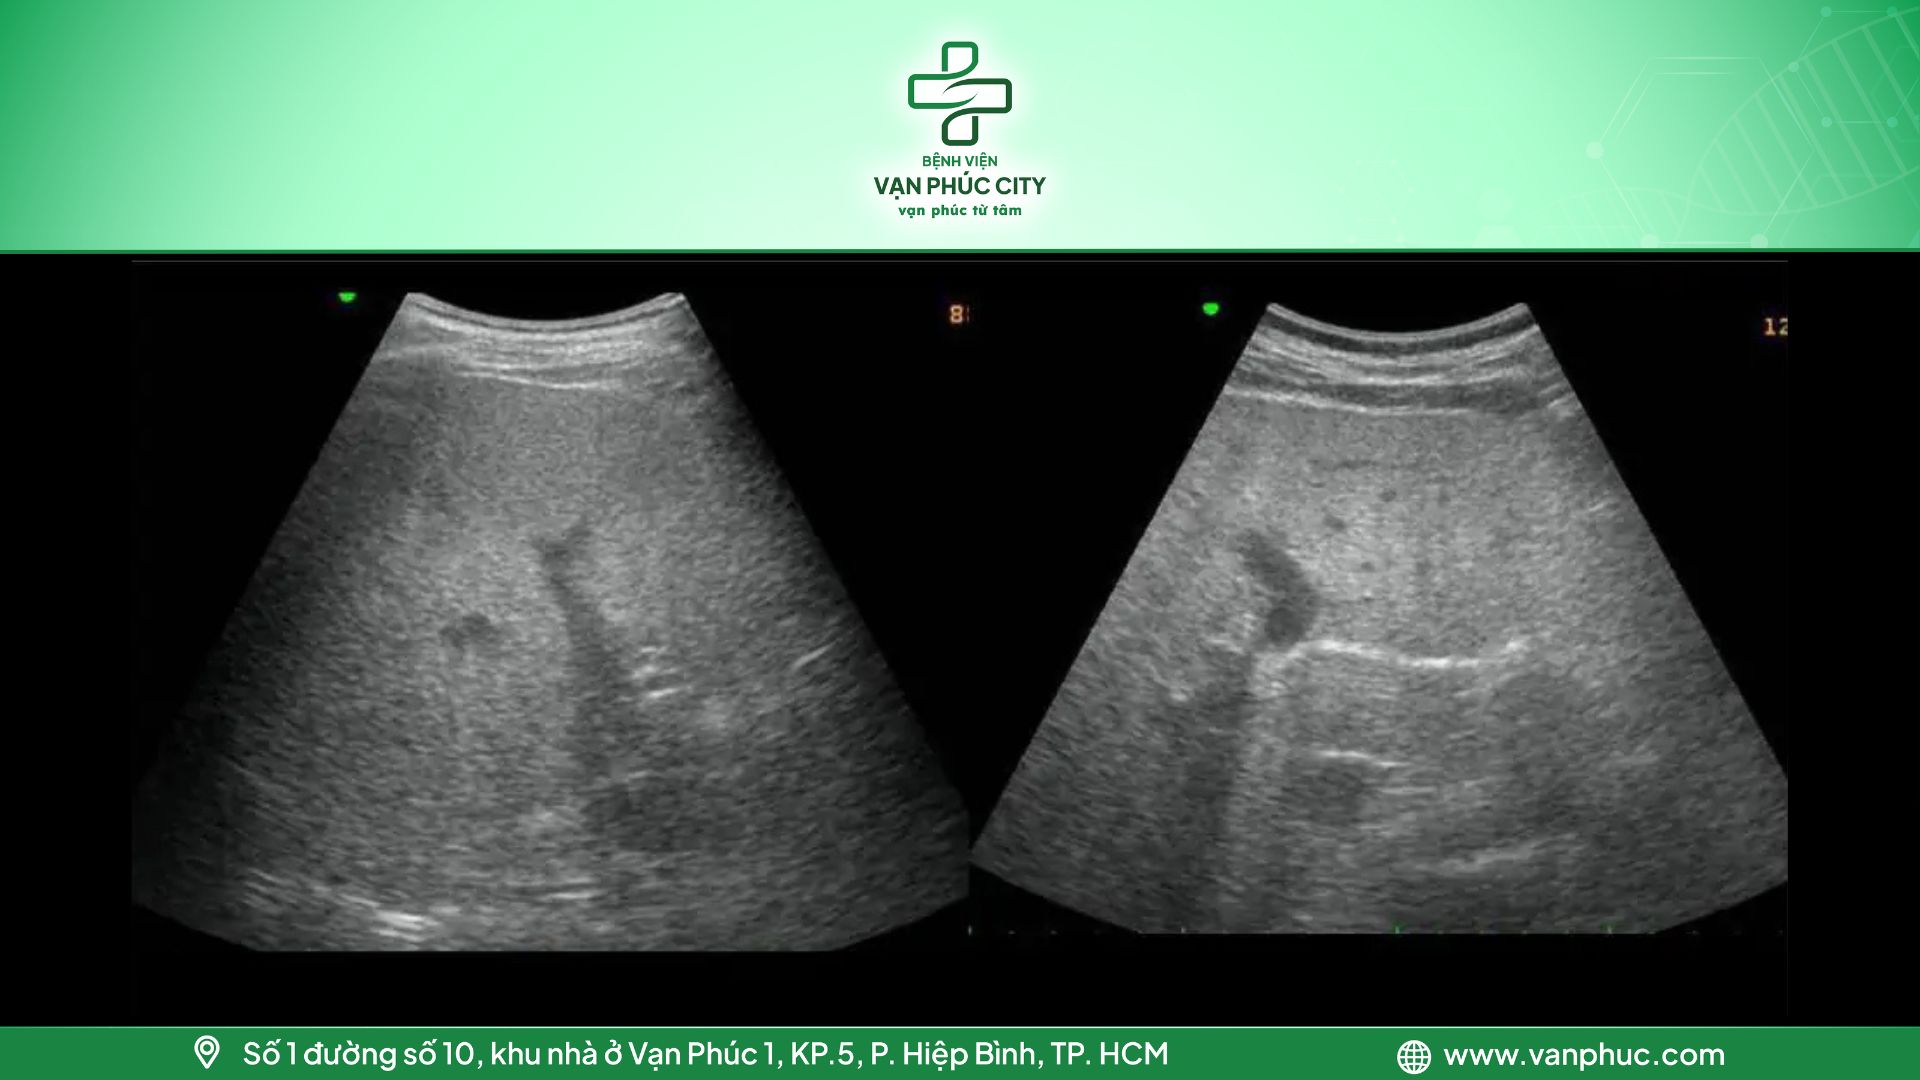

2.2. Gan nhiễm mỡ cấp độ 2

Khi lượng mỡ trong gan chiếm từ 10-25%, hình ảnh siêu âm sẽ cho thấy độ hồi âm lan tỏa và sự hút âm mạnh mẽ từ nhu mô gan. Tuy mức độ thay đổi rõ rệt, nhưng vẫn có thể xác định được vị trí của cơ hoành và các đường bờ tĩnh mạch của gan, mặc dù chúng có thể hơi mờ.

Hình 3: Gan nhiễm mỡ cấp độ 2